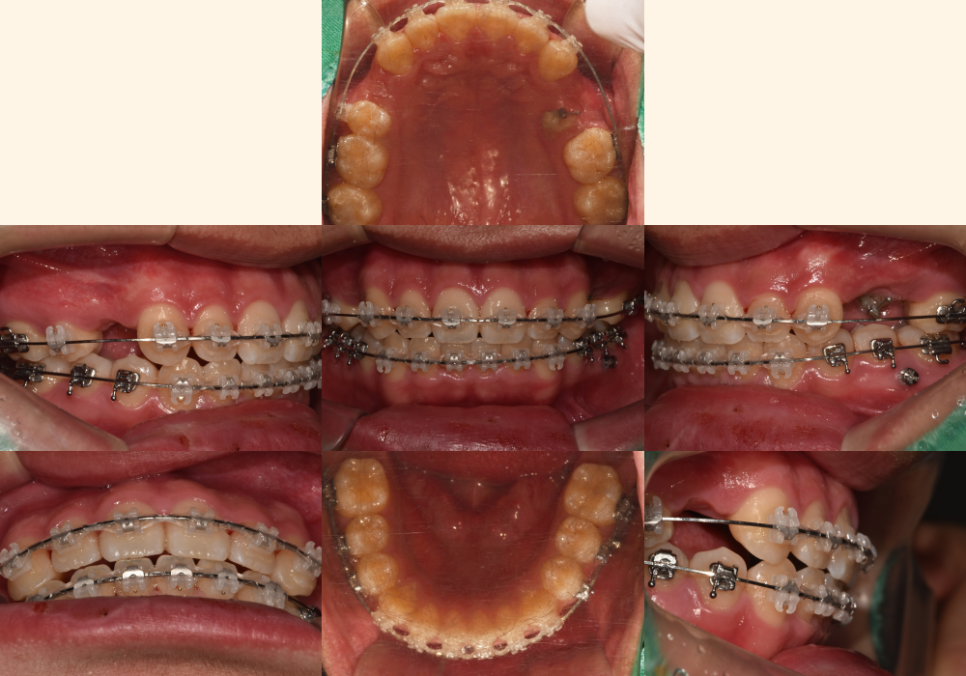

22.08.12

매복된 치아를 끌어내기 위한

공간을 만드는 과정입니다.

첫 번째 작은 어금니를 발치하여

필요한 공간을 확보해요.

이 치아는 저작 기능이 상대적으로 낮고,

발치 후 공간을 닫기에도 유리한 위치에 있습니다.

[매복치 견인]

23.02.25

잇몸을 살짝 절개하여 매복된 치아에

교정 장치를 부착하고,

미니스크류나 기타 고정원을 이용해

서서히 정상 위치로 끌어내는 과정이죠.

23.06.23 // 23.11.25

이 과정에서는

이가 올바른 방향으로 나오도록

정기적인 조정과 관찰이 필수입니다.